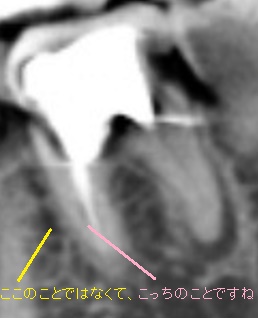

自己分析の予想画像を貼ります。

担当医には、4根管は絶対で、ひねくれの私の歯なので5根管あるかもしれませんよ〜と伝えて探してもらおうと思っています(笑)

このコアを外してくれる歯科が見つからないので、元々長年通院していた歯科に行って相談しようと考えてます。ただ、マイクロスコープがない歯科なので、4根管よう見つけない可能性があるため患者の私から予め4根管見つけてくださいと言っておこうと思っています。

万が一、ルーペだけでよう見つけなかったら、コアさえ無事外してもらえたら、マイクロスコープ保有している歯科で根管を探してもらったらいいので移ろうと考えてます。